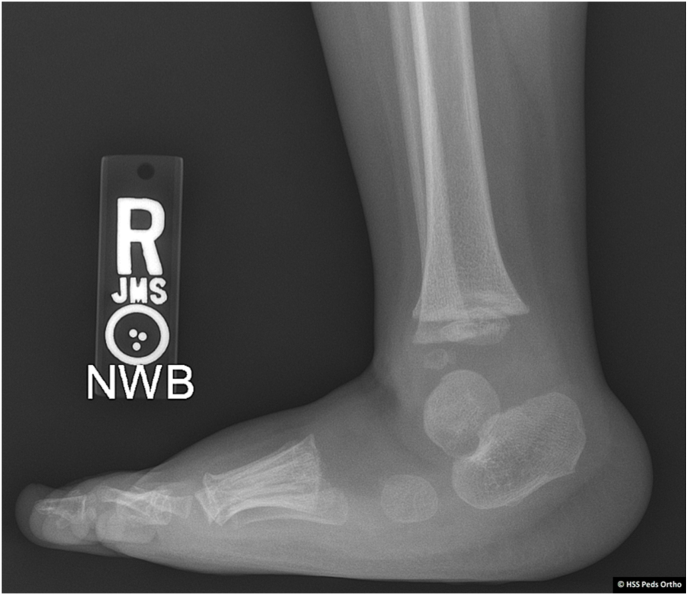

Key concepts: (1)Ponseti casting addresses all elements of clubfoot (midfoot cavus, forefoot and midfoot adduction, hindfoot varus, and equinus) in a systematic way that respects the natural kinematics of the foot.(2)Ponseti casting requires the use of gentle manipulation through the appropriate anatomical regions of the foot to ensure adequate correction, minimize residual deformity, and avoid iatrogenic deformity.(3)Efforts to minimize infantile distress will maximize the success of the Ponseti method. These include choosing appropriate cast and padding materials, providing a succinct casting plan, and optimizing brace tolerance.(4)Common undesirable consequences of casting include cast slippage, skin maceration, and iatrogenic deformities, such as tarsometatarsal abduction, hindfoot valgus, rocker bottom foot, and flat-top talus.